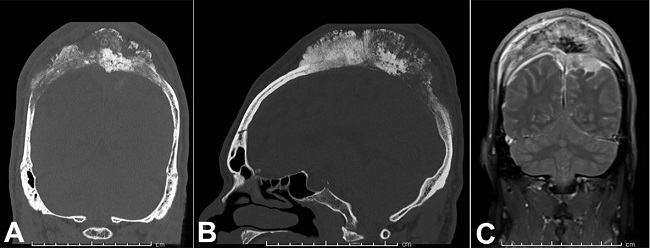

Computed tomography (CT) of the head showed a large midline permeative calvarial lesion measuring 14 × 11.7 × 5.4 cm, with extensive periosteal reaction, subjacent dural thickening, extension into the subcutaneous soft tissues and intracranial extension into the bilateral parietal extra-axial space (Figure 3).

Magnetic resonance imaging (MRI) post-gadolinium fat-saturated T1 sequence showed a large intraosseous mass with demonstration of intracranial extension, invasion into the superior sagittal sinus and regional dural thickening and enhancement (Figure 3). The favored pre-operative clinical diagnosis was osteosarcoma.